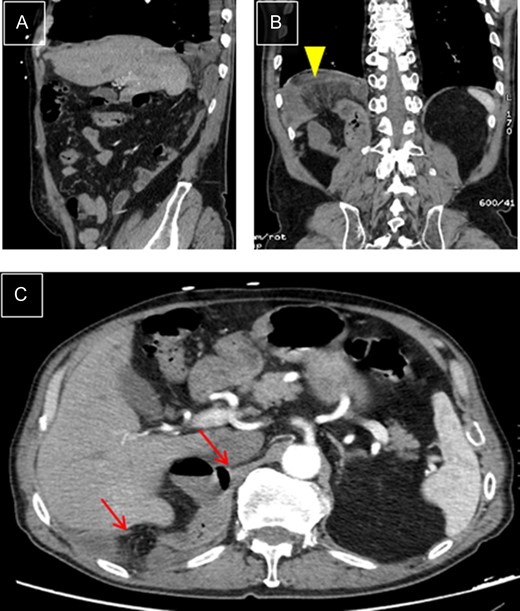

This is a 76-year-old male who came to the Emergency Department with intense periumbilical abdominal pain radiating to the back and vomiting. The patient underwent a right laparoscopic radical nephrectomy 18 days before. There were no complications during the procedure and post-operative period. Physical examination showed right basal hypoventilation with abdominal pain and tenderness in the right upper quadrant. A CT scan showed an orifice in the right diaphragm, through which intestinal loops passed into the thorax, which were dilated and with signs of ischemia (Fig. 1), image not present in the pre-operative CT. The patient underwent emergency surgery, via a right subcostal laparotomy. A diaphragmatic hernia ~6 cm in size was found in the right posterior costophrenic angle with a nonviable loop of ileum, reduced and resected after mobilization of the right hepatic lobe. The orifice was closed with interrupted tension-free stitches. Post-operative recovery was uneventful. One year after the surgery, the patient is asymptomatic and shows no signs of hernia recurrence.

Right diaphragmatic hernia. (A) Thoracic-abdominal CT angiography, sagittal cut, showing right posterior location. (B) Coronal cut: Ileal loop in supradiaphragmatic position (arrowhead). (C) Transverse cut: edges of hernial ring (arrows).